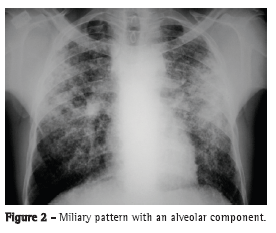

The most common radiological findings are reticular infiltrates and consolidation,(5,6,10,15,17) and cavitation can occur in 27-50% of cases.(6,10,16) Figures 1 to 4 show some of the main radiological patterns in this context.

The leading cause of ICU admission was respiratory failure, and Acute Physiology and Chronic Health Evaluation II (APACHE II) scores ranged from 13 to 23 in most of the studies.(5,6,10,15,17) Some authors evaluated the factors associated with the development of respiratory failure and the need for MV. Gram-negative pneumonia or sepsis, COPD, history of poor compliance with tuberculosis treatment, and cancer were predictors of respiratory failure.(9) In a series of 13 cases, 7 and 6 patients, respectively, had miliary/disseminated tuberculosis and tuberculous pneumonia requiring intensive care. Patients with miliary/disseminated tuberculosis were more likely to require MV than were those with tuberculous pneumonia (18.9% vs. 0.8%; p < 0.0001).(8)